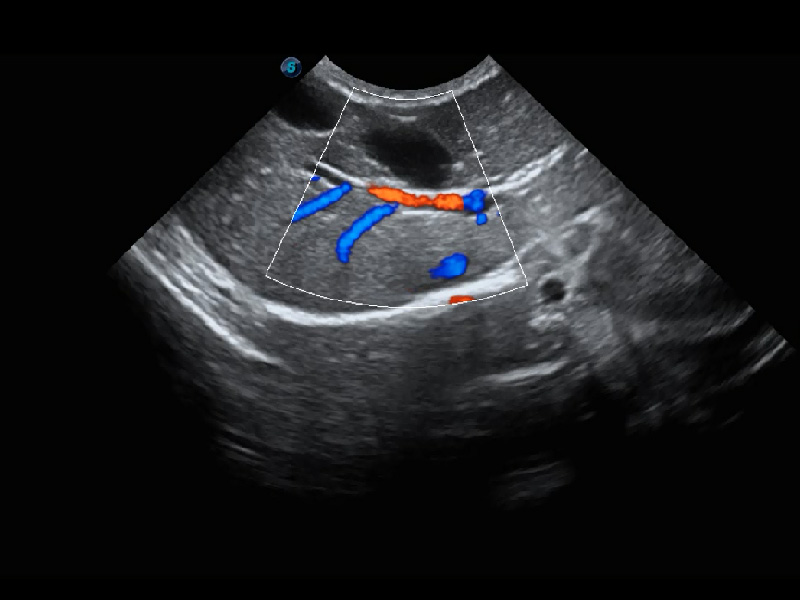

4T血流成像 微察秋毫

融合不同血流成像技术的优势,即可以提升血流成束性,同时可提高血流的视觉敏感性。

PDI 能量多普勒血流

提供高灵敏度和空间分辦率的血流图像,获得更加真实和丰富的诊断信息。

优异的基础图像

(猫)髂动脉血流频谱